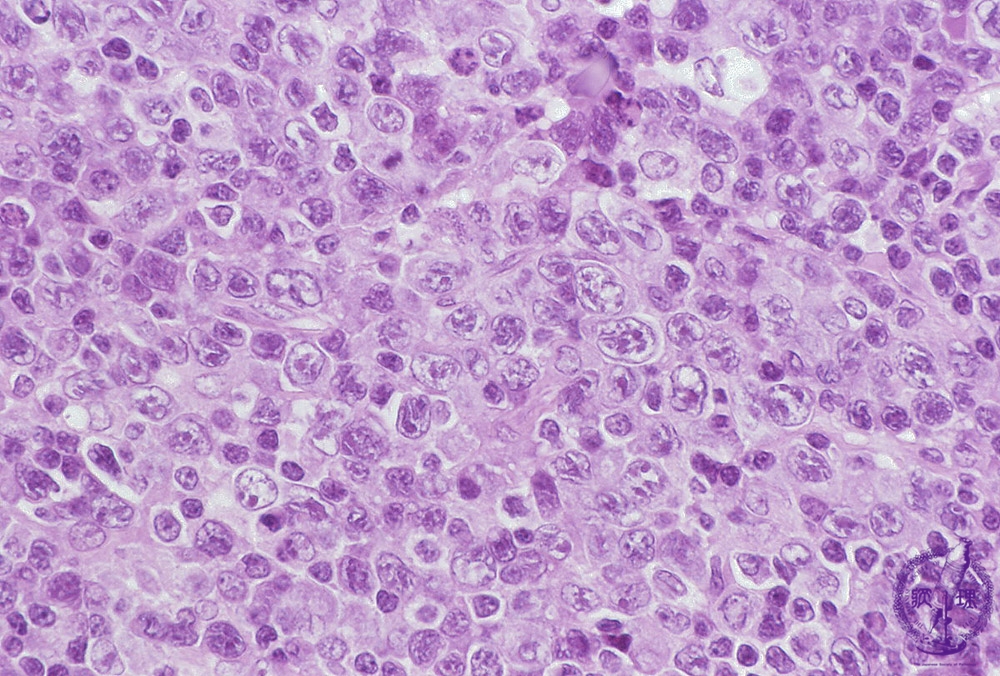

T細胞リンパ腫の診断

T 細胞リンパ腫を診断する場合、医師はおそらく、腫れたリンパ節などの異常な組織片から生検を採取します。

組織が切除され、検査によってリンパ腫の種類が特定されます。